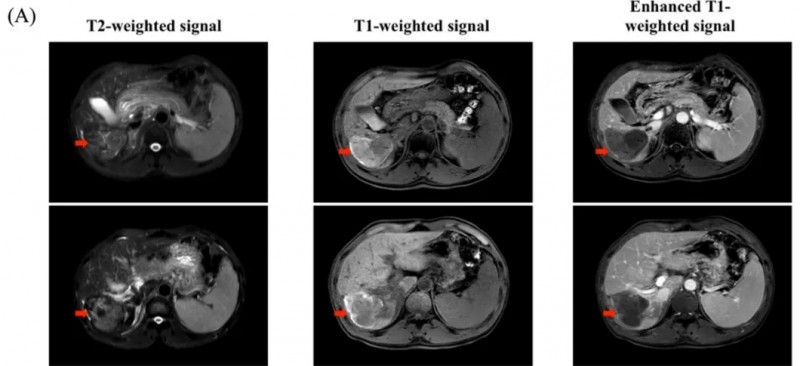

国际知名期刊《Cancer Communications》,曾报道过CAR-GPC3 T细胞治疗晚期肝细胞癌获得长期生存的振奋案例。

该患者是一位50岁男性,确诊为肝细胞癌,且经多种治疗无效,病情持续进展,遂入组接受CAR-GPC3 T细胞治疗。结果显示:治疗6个月后,影像学肿瘤迹象消失,AFP(甲胎蛋白)恢复正常,更为惊喜的是,目前该患者已无癌生存长达8年!